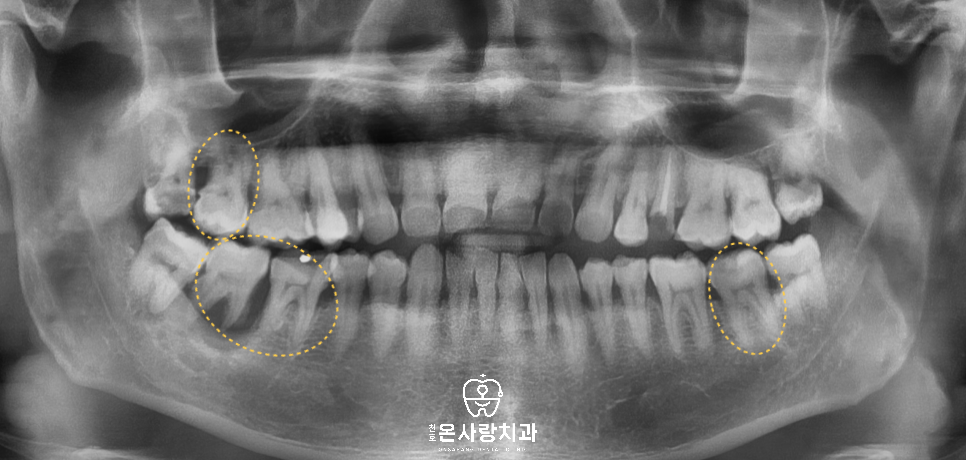

내원 당시 초진 전체 x-ray를

살펴보도록 하겠습니다.

사랑니를 보면 다른 치아와비교했을 때

맹출방향이나 위치가 정위치에 있습니다.

그러나 사랑니 앞의 어금니를 살펴보면

오른쪽 위와 왼쪽 아래의 경우는

사랑니와 맞닿아있던 뒤쪽 부분의

우식이 옆에서부터 깊이

진행된 것을 볼 수 있습니다.

오른쪽 아래의 경우에는

앞쪽의 치조골이 상당히 흡수되어

앞쪽 두개의 큰 어금니에

걸쳐 영향을 주고 있었습니다.